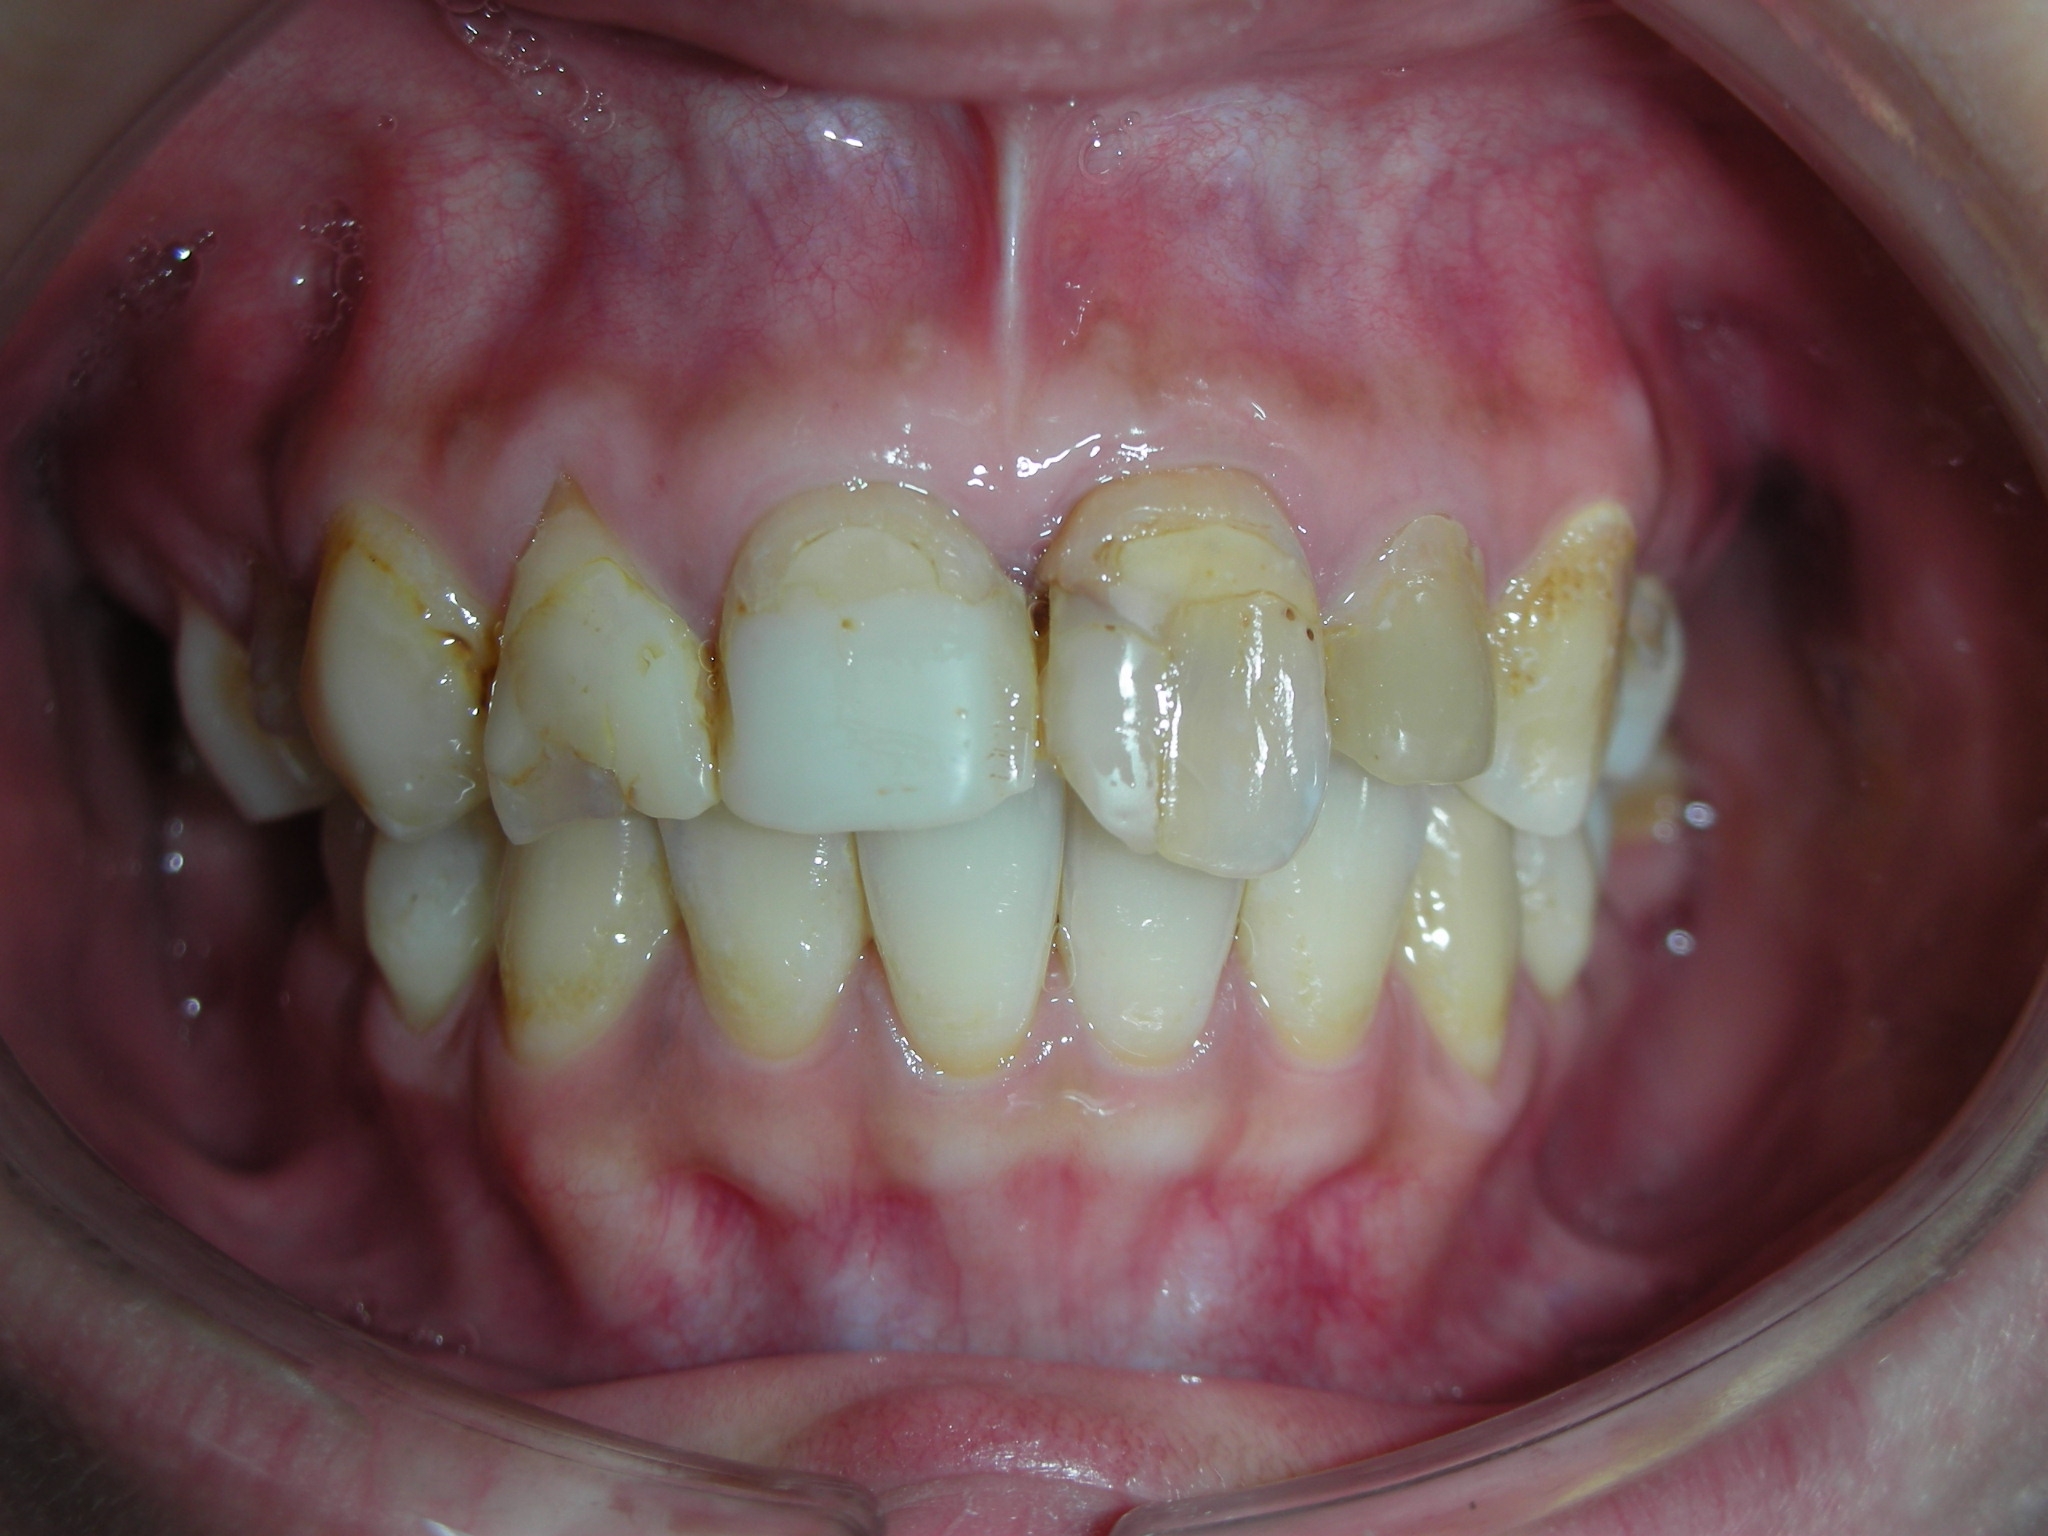

審美牙科 – 前牙美觀評估分

審美牙科

全瓷冠